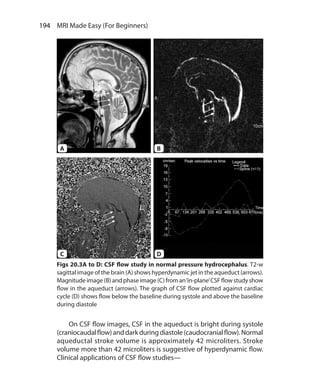

• 14.

xx  MRI MadeEasy (for Beginners) Imaging Planes 173 Clinical Applications of CMRI 176 Chapter 19.  Magnetic Resonance Cholangiopancreatography 183 Principles 183 Sequences used in MRCP 183 MRCP Protocol and Technique 185 Clinical Applications of MRCP 186 Chapter 20.  Miscellaneous Neuroimaging MR Techniques 190 fMRI : Functional MRI 190 Susceptibility Weighted Imaging 192 Cerebrospinal Fluid Flow Study 192 Chapter 21.  Miscellaneous Body Imaging MR Techniques 196 Magnetic Resonance Enterography 196 MR Urography 198 Iron Overload Imaging 199 Magnetic Resonance Elastography 201 Magnetic Resonance Arthrography 201 Index 203–208

• 15.

Basic Principles CHAPTER 1 Four basicsteps are involved in getting an MR image— 1. Placing the patient in the magnet 2. Sending Radiofrequency (RF) pulse by coil 3. Receiving signals from the patient by coil 4. Transformation of signals into image by complex processing in the computers. Now let us understand these steps at molecular level. Present MR imaging is based on proton imaging. Proton is a positively charged particle in the nucleus of every atom. Since hydrogen ion (H+ ) has only one particle, i.e. proton, it is equivalent to a proton. Most of the signal on clinical MR images comes from water molecules that are mostly composed of hydrogen. How do protons help in MR imaging? Protons are positively charged and have rotatory movement called spin. Any moving charge generates current. Every current has a small magnetic field around it. So every spinning proton has a small magnetic field around it, also called magnetic dipole moment. Normally the protons in human body (outside the magnetic field) move randomly in any direction. When external magnetic field is applied, i.e. patient is placed in the magnet, these randomly moving protons align (i.e. their magnetic moment align) and spin in the direction of external magnetic field. Some of them align parallel and others anti-parallel to the external magnetic field.When a proton aligns along external magnetic field, not only it rotates around itself (called Section 1 Ch-1.indd 1 25-09-2012 09:53:45

• 16.

2  MRI MadeEasy (For Beginners) spin) but also its axis of rotation moves forming a‘cone’.This movement of the axis of rotation of a proton is called as precession (Fig. 1.1). The number of precessions of a proton per second is called precession frequency. It is measured in Hertz. Precession frequency is directly proportional to strength of external magnetic field. Stronger the external magnetic field, higher is the precession frequency. This relationship is expressed by Larmors equation— Wo = γ Bo Where wo = Precession frequency in Hz Bo = Strength of external magnetic field in Tesla γ = Gyromagnetic ratio, which is specific to particular nucleus Precession frequency of the hydrogen proton at 1, 1.5 and 3 Tesla is roughly 42, 64 and 128 MHz respectively. Longitudinal Magnetization Let us go one step further and understand what happens when protons align under the influence of external magnetic field. For the orientation in space consider X, Y, and Z axes system. External magnetic field is directed along the Z-axis. Conventionally, the Z-axis is the long axis of the patient as well as bore of the magnet. Protons align parallel and Fig. 1.1: Spin versus precession. Spin is rotation of a proton around its own axis while precession is rotation of the axis itself under the influence of external magnetic field such that it forms a‘cone’ Ch-1.indd 2 25-09-2012 09:53:45

• 17.

3  Basic Principles antiparallelto external magnetic field, i.e. along positive and negative sides of the Z-axis. Forces of protons on negative and positive sides cancel each other. However, there are always more protons spinning on the positive side or parallel to Z-axis than negative side. So after canceling each others forces there are a few protons on positive side that retain their forces. Forces of these protons add up together to form a magnetic vector along the Z-axis. This is called as longitudinal magnetization (Fig. 1.2). Longitudinal magnetization thus formed along the external magnetic field can not be measured directly. For the measurement it has to be transverse. Transverse Magnetization As discussed in the previous paragraph when patient is placed in the magnet, longitudinal magnetization is formed along the Z-axis. The next step is to send radiofrequency (RF) pulse. The precessing protons pick up some energy from the radiofrequency pulse. Some of these protons go to higher energy level and start precessing antiparallel (along negative side of the Z-axis). The imbalance results in tilting of the magnetization into the transverse (X-Y) plane. This is called as transverse magnetization (Fig. 1.3). In short, RF pulse causes titling of the magnetization into transverse plane. The precession frequency of protons should be same as RF pulse frequency for the exchange of energy to occur between protons and RF pulse.When RF pulse and protons have the same frequency protons Fig. 1.2: Longitudinal magnetization Ch-1.indd 3 25-09-2012 09:53:46

• 18.

4  MRI MadeEasy (For Beginners) can pick up some energy from the RF pulse.This phenomenon is called as“resonance”- the R of MRI. RF pulse not only causes protons to go to higher energy level but also makes them precess in step, in phase or synchronously. MR Signal Transverse magnetization vector has a precession frequency. It constantly rotates at Larmor frequency in the transverse plane and induces electric current while doing so.The receiver RF coil receives this current as MR signal (Fig. 1.4).The strength of the signal is proportional to the magnitude of the transverse magnetization. MR signals are transformed into MR image bycomputers using mathematical methods such as Fourier Transformation. Revision: Basic four steps of MR imaging include: 1. Patient is placed in the magnet— All randomly moving protons in patent’s body align and precess along the external magnetic field. Longitudinal magnetization is formed long the Z-axis. 2. RF pulse is sent— Precessing protons pick up energy from RF pulse to go to higher energy level and precess in phase with each other. This results in reduction in longitudinal magnetization and formation of transverse magnetization in X-Y plane. Fig. 1.3: Transverse magnetization. Magnetization vector is flipped in transverse plane by the 90 degree RF pulse Ch-1.indd 4 25-09-2012 09:53:46